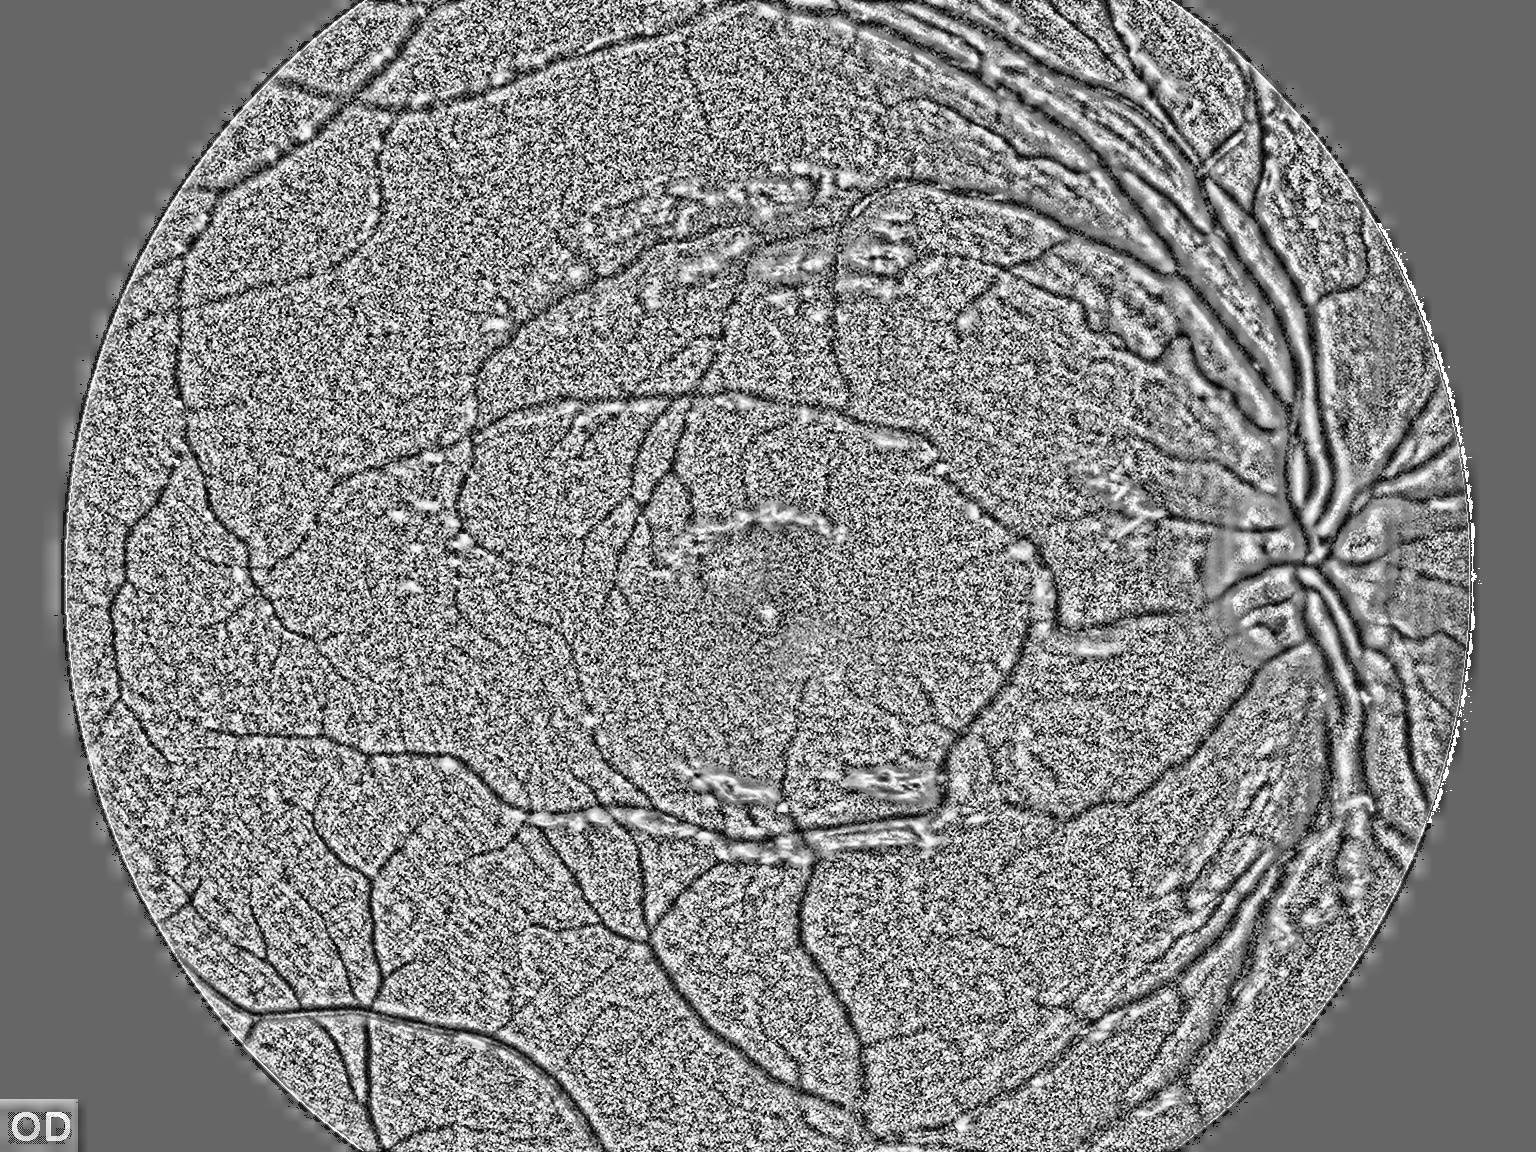

我试图从图像中提取血管,为此,我首先对图像进行均衡化,应用CLAHE直方图获得以下结果:

clahe = cv2.createCLAHE(clipLimit=100.0, tileGridSize=(100,100))

self.cl1 = clahe.apply(self.result_array)

self.cl1 = 255 - self.cl1